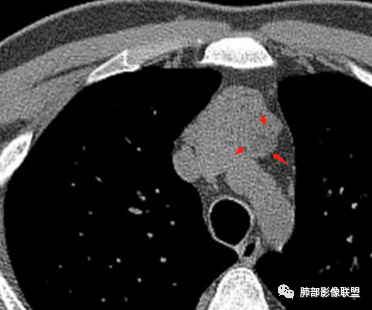

南边分析-征象标注

年轻男性,双下肌乏力,可惜没交代是啥手术,是不是前纵隔病变手术。

* 整个形态就是胸腺的形态,定位在前纵隔,胸腺病变应该可以。26岁男性,这么年轻,胸腺源性肿瘤几率比较低,

2、下半部分,形态自然,边缘稍膨隆,内部密度实性夹杂稍低密度影,而且是线样低密度影,比较自然走形,支持胸腺组织增生或残留。如果其他肿瘤所致,应该是边缘膨隆,类圆形,内部密度均匀,或部分区域坏死,或者结节状灶之间间隔。所以这个首先:胸腺增生或残留应该有。

* 部分区域边缘平直、稍凹陷,部分密度较低,边缘稍膨隆。

* 部分密实。因为没有增强,附近血管分不开,内部密度差不是那么明显,但是有密度差。提示:内部组织结构有变化,不是单一的组织结构。